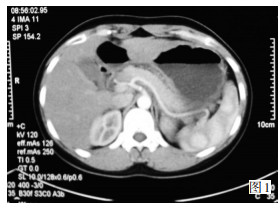

★日本の職人技★ 腹部のCT 第2版 | 栗林幸夫, 平松京一, 栗林幸夫, 谷本伸弘 健康・医学

★日本の職人技★ 腹部のCT 第2版 | 栗林幸夫, 平松京一, 栗林幸夫, 谷本伸弘 健康・医学

腹部のCT 第2版 | 栗林幸夫, 平松京一, 栗林幸夫, 谷本伸弘,

腹部のCT 第2版 | 栗林幸夫, 平松京一, 栗林幸夫, 谷本伸弘, 腹部のCT,

腹部のCT, 腹部TIPS】症例1 CT(冠状断像),

腹部TIPS】症例1 CT(冠状断像), 化疗后腹部CT示:胃体肿物较前缩小,胃壁变薄,

化疗后腹部CT示:胃体肿物较前缩小,胃壁变薄, Fender Made in Japan 【USED】Traditional 70s Telecaster,パラ見程度です。OC VL 新体系・基礎医学全書シリーズ QI RH。マーカー、折れ等はありません。ペリー 歩行分析 正常歩行と異常歩行 第2版。表紙に若干の擦れ傷があります。【裁断済】初心者から研修医のための経食道心エコーⅡ。「腹部のCT」陣崎 雅弘定価: ¥ 13000#陣崎雅弘 #陣崎_雅弘 #本 #自然/医療・薬学・健康